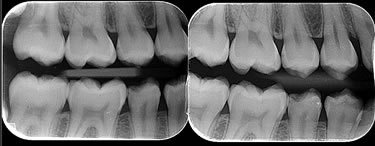

Interproximal